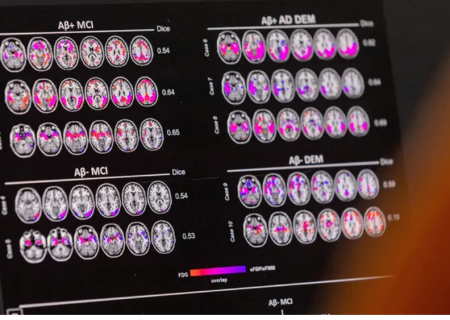

آلزایمر

مطالعه محققان در باره تاثیر پروتئین ها در رابطه با زوال عقل

در حال حاضر، اسکن مغز میتواند سطوح غیرطبیعی پروتئینی به نام بتا آمیلوئید را سالها قبل از ایجاد زوال عقل آلزایمر تشخیص دهد، اما این آزمایشها پرهزینه هستند و اغلب تحت پوشش بیمه نیستند.